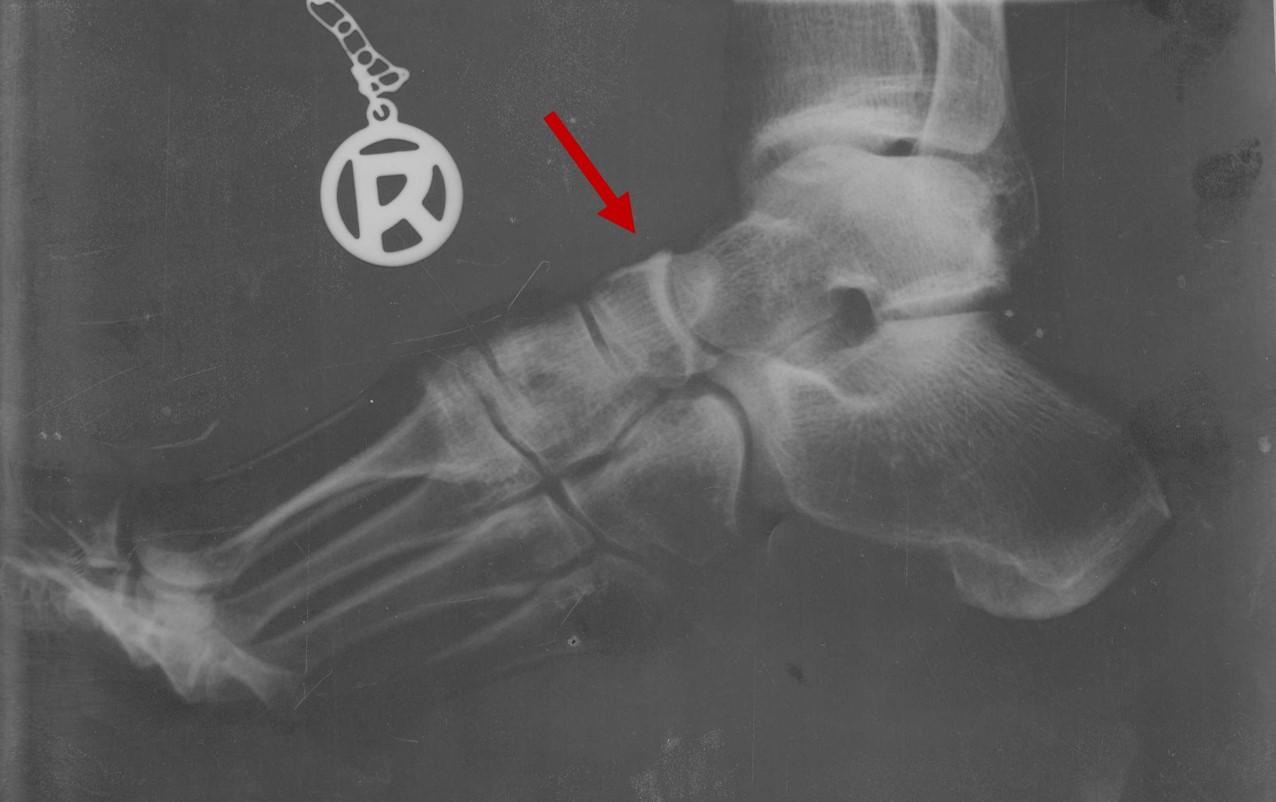

Sinn oder Unsinn bildgebender Verfahren

Bei bildgebenden Verfahren, wie z.B. einem Röntgenbild, wird vor allem im fortgeschrittenen Alter immer eine Verschmälerung des Gelenkspaltes sichtbar werden. Auch ungünstige Stellungen der gelenksbildenden Knochen sind auf den Bildern zu sehen.

Die helle weiße Fläche am Gelenkspalt zeigt die Veränderung und den Abbau des hyalinen Knorpels an.